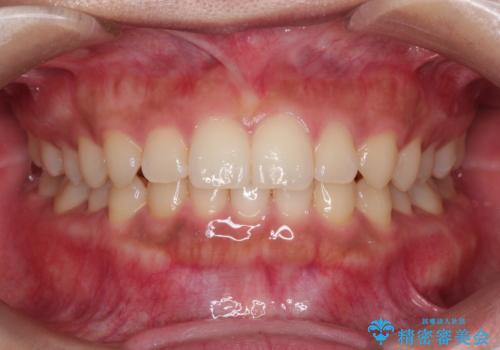

前歯の隙間を閉じたい。インビザラインによる治療

- 前歯の隙間を閉じたいと矯正カウンセリングに来られた患者様です。

マウスピース矯正(インビザライン)を行い短期間で治療が完了しました。